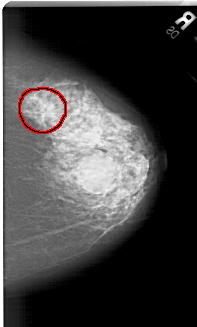

A_1416_1.LEFT_CC

FILE: A_1416_1.RIGHT_CC.OVERLAY

TOTAL_ABNORMALITIES 1

ABNORMALITY 1

LESION_TYPE MASS SHAPE IRREGULAR MARGINS SPICULATED

ASSESSMENT 5

SUBTLETY 4

PATHOLOGY MALIGNANT

TOTAL_OUTLINES 1

BOUNDARY